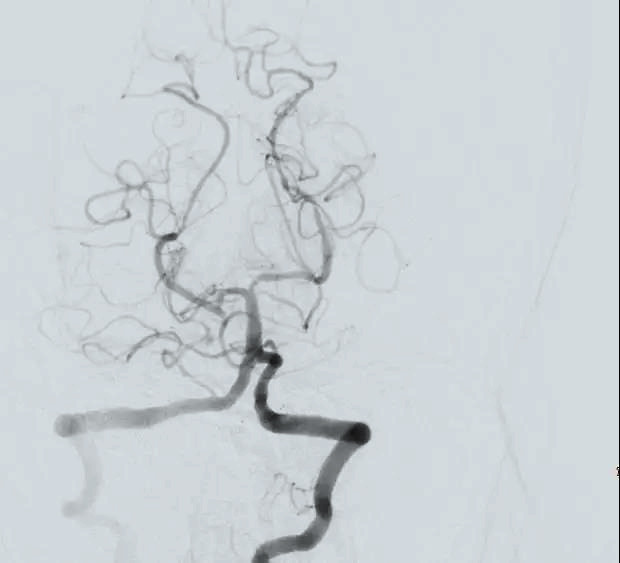

在神經(jīng)外科戴偉民主任的帶領下,李運平、劉榮財醫(yī)生默契配合,團隊協(xié)作為搶救生命爭分奪秒。“全麻及動脈置鞘,基底動脈起始部完全閉塞?!蹦X血管造影再次印證葉女士危在旦夕?!霸偻硪环昼?,后果不堪設想!” DSA導管室,一場與時間賽跑的生命爭奪戰(zhàn)正在進行。定點、介入,從放置取栓裝置到送達栓塞部位,每一個動作都“重若千鈞”,終于在3毫米的動脈導管內(nèi)完整取出5X3毫米的血栓,復查造影,顯示基底動脈血流恢復,取栓成功。而此時,距離葉女士抵達DSA導管室,僅僅過去了20分鐘。

取栓前

取栓后